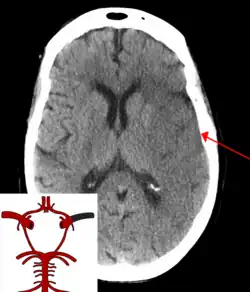

![]() | |

| CT scan of the brain showing a massive, prior right-sided ischemic stroke from blockage of an artery. Changes on a CT may not be visible early on.[1] | |

The most significant risk factor for stroke is high blood pressure.[7] Other risk factors include high blood cholesterol, tobacco smoking, obesity, diabetes mellitus, a previous TIA, end-stage kidney disease, and atrial fibrillation.[2][7][8] Ischemic stroke is typically caused by blockage of a blood vessel, though there are also less common causes.[13][14][15] Hemorrhagic stroke is caused by either bleeding directly into the brain or into the space between the brain's membranes.[13][16] Bleeding may occur due to a ruptured brain aneurysm.[13] Diagnosis is typically based on a physical exam and supported by medical imaging such as a CT scan or MRI scan.[9] A CT scan can rule out bleeding, but may not necessarily rule out ischemia, which early on typically does not show up on a CT scan.[10] Other tests such as an electrocardiogram (ECG) and blood tests are done to determine risk factors and possible causes.[9] Low blood sugar may cause similar symptoms.[9]

Stroke is diagnosed through several techniques: a neurological examination (such as the NIHSS), CT scans (most often without contrast enhancements) or MRI scans, Doppler ultrasound, and arteriography. The diagnosis of stroke itself is clinical, with assistance from the imaging techniques. Imaging techniques also assist in determining the subtypes and cause of stroke. There is yet no commonly used blood test for the stroke diagnosis itself, though blood tests may be of help in finding out the likely cause of stroke.[76] In deceased people, an autopsy of stroke may help establishing the time between stroke onset and death.

For diagnosing ischemic (blockage) stroke in the emergency setting:[77]

- CT scans (without contrast enhancements)

- sensitivity= 16% (less than 10% within first 3 hours of symptom onset)

- specificity= 96%

- MRI scan

- sensitivity= 83%

- specificity= 98%

For diagnosing hemorrhagic stroke in the emergency setting:

- sensitivity= 89%

- specificity= 100%

- sensitivity= 81%

For detecting chronic hemorrhages, an MRI scan is more sensitive.[78]

CT scans may not detect ischemic stroke, especially if it is small, of recent onset,[10] or in the brainstem or cerebellum areas (posterior circulation infarct). MRI is better at detecting a posterior circulation infarct with diffusion-weighted imaging.[79] A CT scan is used more to rule out certain stroke mimics and detect bleeding.[10] The presence of leptomeningeal collateral circulation in the brain is associated with better clinical outcomes after recanalization treatment.[80] Cerebrovascular reserve capacity is another factor that affects stroke outcome – it is the amount of increase in cerebral blood flow after a purposeful stimulation of blood flow by the physician, such as by giving inhaled carbon dioxide or intravenous acetazolamide. The increase in blood flow can be measured by PET scan or transcranial doppler sonography.[81] However, in people with obstruction of the internal carotid artery of one side, the presence of leptomeningeal collateral circulation is associated with reduced cerebral reserve capacity.[82]